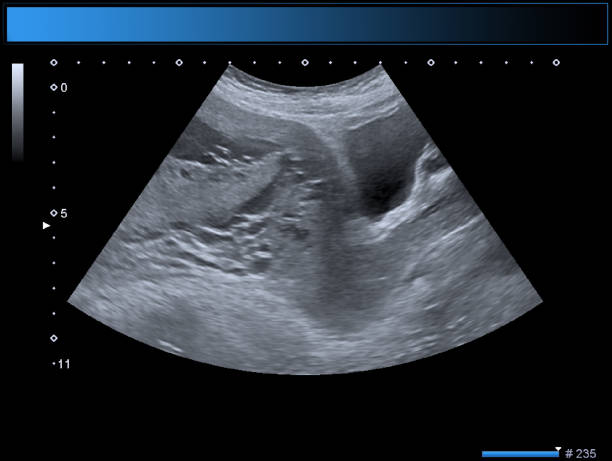

The TIFFA scan in pregnancy is usually performed between 18 to 22 weeks and provides valuable insights into the baby’s anatomy. This ultrasound helps doctors at Dr. Aravind’s IVF confirm that the fetal growth aligns with the gestational age and that no abnormalities are present, ensuring peace of mind for expecting parents.

During the TIFFA scan procedure, a skilled sonographer gently moves the ultrasound probe across the abdomen to capture detailed images of the fetus. The TIFFA scan uses go beyond diagnosis — they also help doctors plan for safe delivery and detect any complications early. For those seeking accurate results and compassionate guidance, the Best Fertility centre in Chennai, Dr. Aravind’s IVF, offers a perfect blend of medical precision and emotional support, making sure every parent feels confident and informed through each step of pregnancy care.